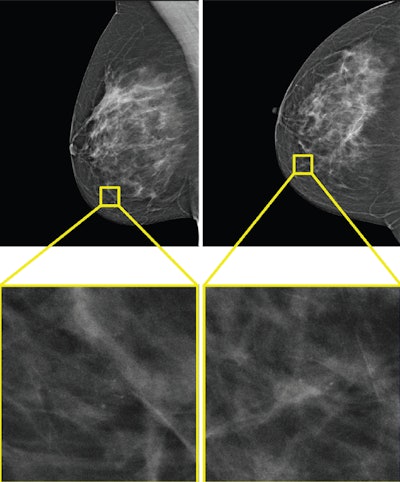

The only example of a screening exam with a screen-detected cancer that would have been missed by AI in a hybrid reading strategy based on the AI uncertainty score of the entropy of the mean probability of malignancy (PoM) score of the most suspicious region. During screening, a 52-year-old woman was recalled following arbitration scoring of the right breast as Breast Imaging Reporting and Data System (BI-RADS) 4 after the first and second radiologists scored the right breast as BI-RADS 1 and 4, respectively. This woman would not have been recalled if the examination was read by the AI model, which assigned a PoM score of 30, which would be classified as a certain prediction with an uncertainty quantification of 0.57. Both the mediolateral oblique (left) and craniocaudal (right) views of the affected breast are shown. The boxes indicate the calcifications found during screening, and the final diagnosis of this examination was ductal carcinoma in situ.The only example of a screening exam with a screen-detected cancer that would have been missed by AI in a hybrid reading strategy based on the AI uncertainty score of the entropy of the mean probability of malignancy (PoM) score of the most suspicious region. During screening, a 52-year-old woman was recalled following arbitration scoring of the right breast as Breast Imaging Reporting and Data System (BI-RADS) 4 after the first and second radiologists scored the right breast as BI-RADS 1 and 4, respectively. This woman would not have been recalled if the examination was read by the AI model, which assigned a PoM score of 30, which would be classified as a certain prediction with an uncertainty quantification of 0.57. Both the mediolateral oblique (left) and craniocaudal (right) views of the affected breast are shown. The boxes indicate the calcifications found during screening, and the final diagnosis of this examination was ductal carcinoma in situ.RSNA